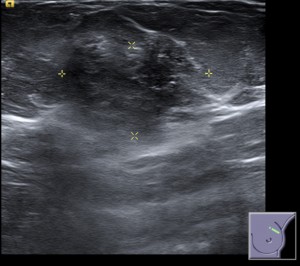

Ante estos hallazgos, la prueba complementaria a realizar sería la ecografía, para valorar mejor el nódulo. Observamos un nódulo heterogéneo, isoecogénico y palpable en CSE MI, de márgenes parcialmente definidos, de alta sospecha de malignidad y asociados a cambios inflamatorios regionales.

El diagnóstico fue un nódulo BIRADS 4 en CSE MI, palpable, con cambios inflamatorios asociados en ecografía. Se realizó una BAG. Se necesitarían los resultados de anatomía patológica para poder dar un diagnóstico preciso.